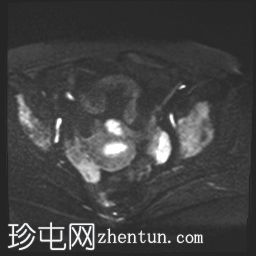

MRI

轴位

DWI

可见膀胱左侧壁有一边界清晰的T2低信号实

性病

灶,无扩散受限,均匀强化。未见膀胱周围侵犯或肾积水。

子宫底部前壁可见一小肌瘤。双侧卵巢可见无强化囊肿。盆腔及腹股沟未见异常淋巴结肿大。

这是一例经组织学证实的膀胱平滑肌瘤病例。